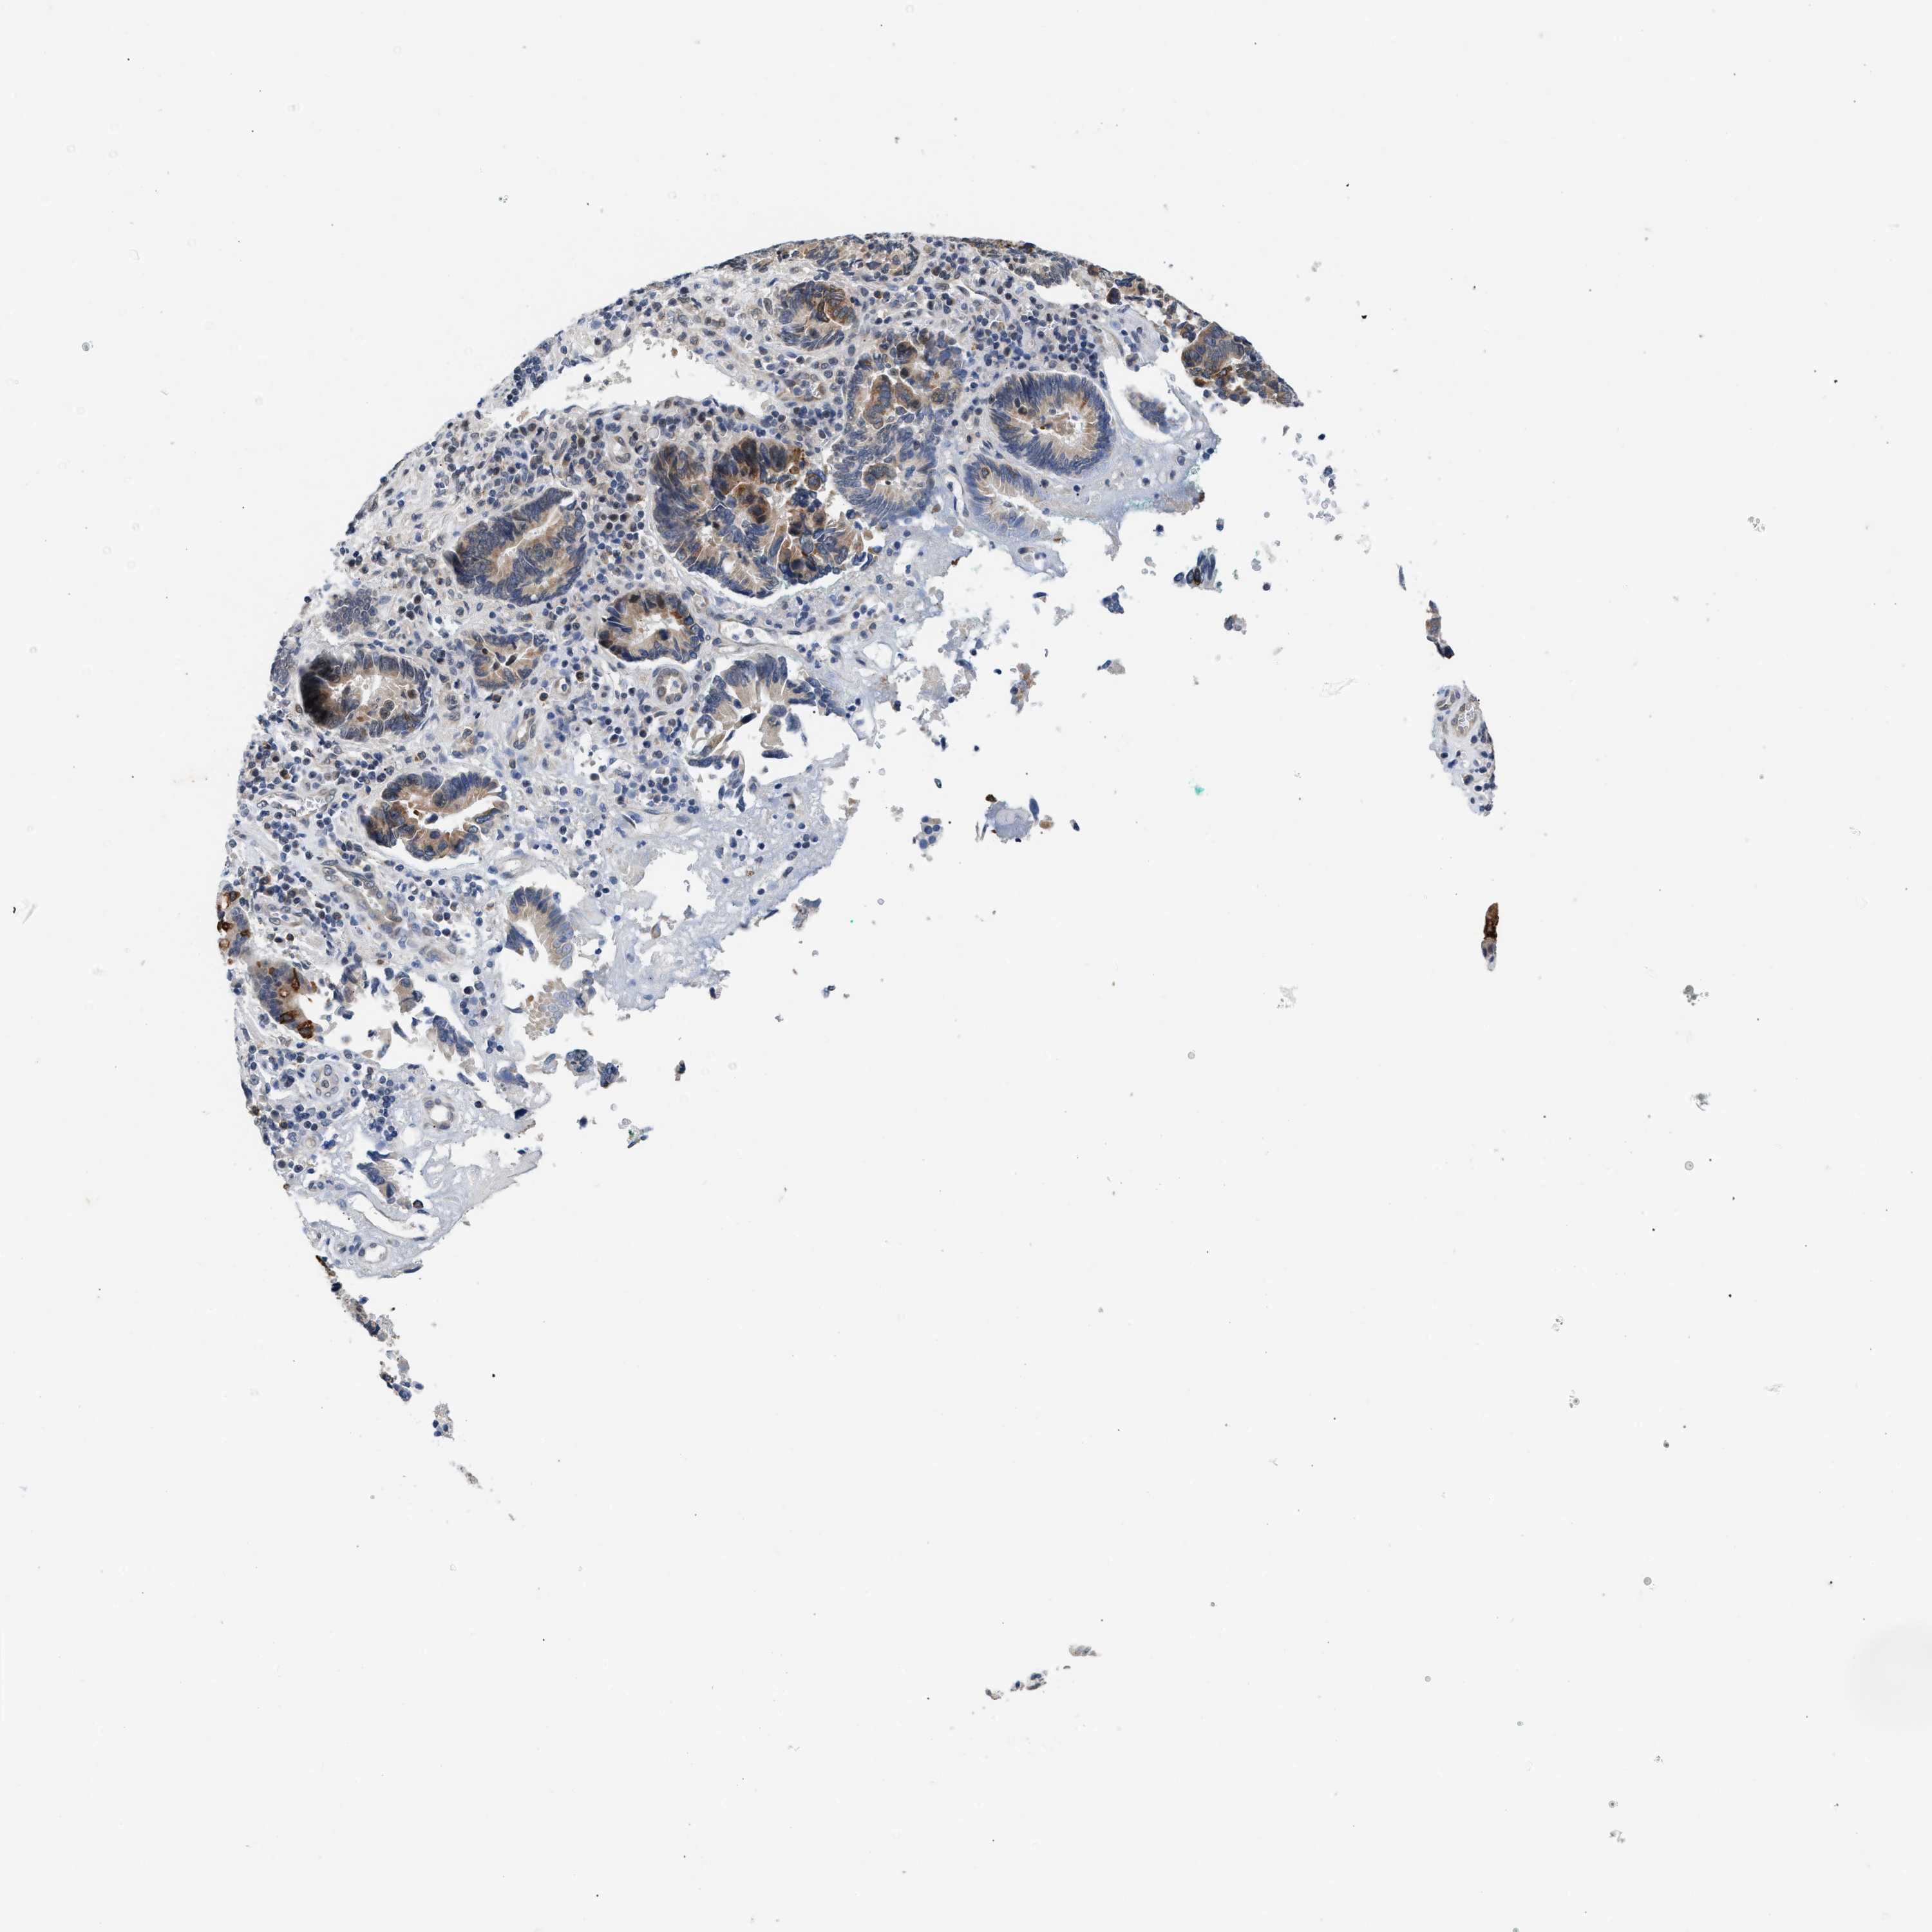

PANCREATIC CANCER - Protein expressioni

A mouse-over function shows sample information and annotation data. Click on an image to view it in a full screen mode. Samples can be filtered based on level of antibody staining by selecting one or several of the following categories: high, medium, low and not detected. The assay and annotation is described here.

Note that samples used for immunohistochemistry by the Human Protein Atlas do not correspond to samples in the TCGA dataset.

Antibody stainingi

Antibody staining in the annotated cell types in the current human tissue is reported as not detected, low, medium, or high, based on conventional immunohistochemistry profiling in selected tissues. This score is based on the combination of the staining intensity and fraction of stained cells.

Each image is clickable and will lead to virtual microscopy that enables deeper exploration of all samples and also displays staining intensity scores, fraction scores and subcellular localization as well as patient and tissue information for each sample.

Antibody CAB020802

Staining

High

Medium

Low

Not detected

Intensity

Strong

Moderate

Weak

Negative

Quantity

>75%

75%-25%

<25%

None

Location

Nuclear

Cytoplasmic/membranous

Cytoplasmic/membranous,nuclear

Adenocarcinoma, NOS